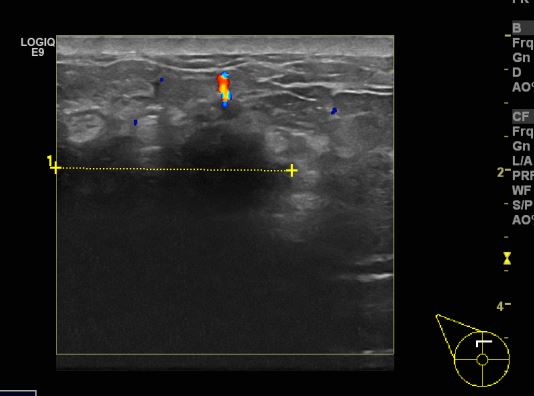

상기환자 40대 여자분으로 한달전부터 만져지는 멍우리 있어 본원 초음파검사후 우측 12시 방향 조직검사 시행한 후  우측유방 침윤성 유관암진단되었습니다.